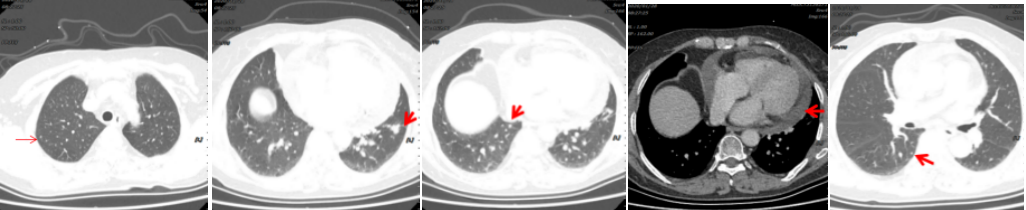

病例简介 该病例是一个肺腺癌(cT4N0M1a)IVa期患者,合并有高血压、冠心病、糖尿病。一线治疗前基因检测结果提示EGFR 19del(+)。一线治疗(埃克替尼片125mg tid)疗效评估为PR、PFS 22个月。一线治疗前基因检测结果提示EGFR 19Del(+)、T790M(+)。后入组D0316(贝福替尼)在EGFR阳性局部晚期或转移性非小细胞肺癌的II期临床试验(IBIO-102项目)。治疗先后由D0316 75mg qd更改方案为D0316 100mg qd,疗效评估为PR,、PFS>32月。至今患者仍持续用药随访中。 Part 1 基本信息 患者:女性;74岁。 主述:反复咳嗽3年,加重伴呼吸费力4月,于2018-1-17就诊。 既往史: 高血压病史10年,服用络活喜、厄贝沙坦氢氯噻嗪、美托洛尔控制血压;冠心病,冠脉支架置入术后4年;糖尿病史2年;否认其他病史。 Part 2 诊疗经过 治疗前辅助检查 2018-1-17查体:血压129/85mmHg;无明显阳性体征。 实验室检查 2018-1-18:血CEA 9.9ng/ml、Cyfra21-1 4.3ng/ml;SCC、NSE、Pro-grp均正常;血常规(Hb 109g/l)、肝肾功能、crp正常。 影像学检查 2018-1-8胸部CT:两肺多发结节,考虑MT伴转移,对照2017-10-4片增大,冠脉钙化,左侧部分肋骨陈旧性骨折,胆囊结石; 2018-1-22腹部B超:脂肪肝倾向,胆囊结石,两肾囊肿,两侧肾上腺未见明显异常回声; 2018-1-21头颅MRI:平扫+增强未见明显异常; 2018-1-23骨ECT:全身骨显像未见明显转移征象。 治疗前病理诊断 肺腺癌(cT4N0M1a) IVa期; 2018-1-18肺穿刺及病理:CK7( ++++ );NapsinA( ++++ ) ;TIF-1(++++);EGFR 19Del(+) ;ALK(-) 。 治疗前临床诊断 肺腺癌(cT4N0M1a) IVa期;PS 1分;EGFR 19Del(+);冠心病、冠脉支架置入术后;高血压病;糖尿病。 一线治疗 治疗方案:2018-1-26开始,埃克替尼片125mg tid。 疗效评估(PR,PFS 22月 ) 埃克替尼治疗11.3个月,两肺结节减少、缩小,达到PR (2018-12-4);治疗22个月,左下肺结节增大、肺内新发小结节、新发心包积液,出现PD(2019-11-21)。 2018-1-18 治疗前基线 2018-12-4 埃克替尼 11.3月(PR) 2019-11-21 埃克替尼 22月(PD) 一线治疗后辅助检查 实验室检查 2019-11-29血CEA 8.4ng/ml ;Cyfra21-1 4.8ng/ml;SCC、NSE、Pro-grp均正常。 2019-12-13血生化肌酐84umol/l;肝功能正常;血常规正常。 影像学检查 2019-12-4头颅MRI平扫+增强:脑内少许腔梗灶; 2019-12-2骨ECT:全身骨显像未见明显转移征象; 2019-12-4腹部增强CT:胆囊结石,右肾上腺及胰腺钙化灶,两肾囊肿。 生理学检查 2019-12-13 ECG:窦性心律,T波改变; 2019-12-13心超:左室轻度增大,左室壁偏厚,左房轻度增大,轻度肺动脉高压伴轻度三尖瓣返流,心包积液,脏层心包增厚,左室舒张功能轻度减退。 一线治疗后病理诊断 2019-11-29分子病理(ARMS法):EGFR 19Del(+) ;T790M(+)。 临床诊断 肺腺癌(cT4N0M1a);IVa期;肺、心包转移;PS 1分;EGFR 19Del(+);T790M(+);冠心病;冠脉支架置入术后;高血压病;糖尿病;肾功能不全。 二线治疗 入组D0316(贝福替尼)在EGFR阳性局部晚期或转移性非小细胞肺癌的II期临床试验(IBIO-102项目)。 治疗方案 2019-12-19开始D0316 75mg qd,于2019-12-24至2020-1-15出现头痛、肩背痛1级AE,自行缓解; 2020-1-13开始D0316 100mg qd; 合并用药有针对糖尿病药物西格列汀片 50mg qd;针对高血压药物氨氯地平5mg qd、厄贝沙坦氢氯噻嗪片1片qd、美托洛尔缓释片47.5mg qd;针对冠心病药物西洛他唑 50mg bid;针对睡眠障碍药物氯硝西泮片1mg qn、艾司酉酞普兰片10mg qd、喹硫平片50mg qd。 安全性评估 疗效评估(PR, PFS>32月 ) D0316 治疗6周就达到PR,患者左下肺靶病灶缩小,两肺小结节稳定、部分缩小(2020-1-28);治疗30周仍为PR,且心包积液减少(2020-7-13);治疗30.5月仍为PR,右下叶背段胸膜下结节缓慢进展(2022-6-30)。 2019-11-21 D0316 治疗前基线 2020-1-28 D0316 治疗6周(PR) 2020-7-13 D0316 治疗30周(PR) 2022-6-30 D0316 治疗30.5月(PR) 2022-6-30腹部增强CT:胆囊结石,右肾上腺及胰腺钙化灶,两肾囊肿。 目前D0316(贝福替尼) 100mg qd 治疗中, PS 1分。